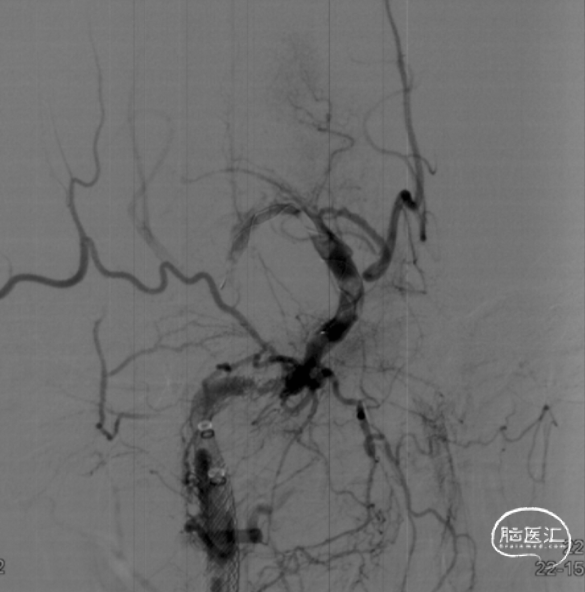

造影见Apollo支架内狭窄伴血栓形成

3*12 NC-trek支架内扩张

再次造影见M1段闭塞,C6段血栓影,考虑血栓向远端移位,但被支架捕获。

拟将抽吸导管越过Apollo支架至血栓近端,但多次尝试CAT7均无法通过支架。后予2/12 NC-trek球囊部分充盈,辅助CAT7通过Apollo支架到达C6段,抽拉结合,取出血栓,随后恢复前向血流。